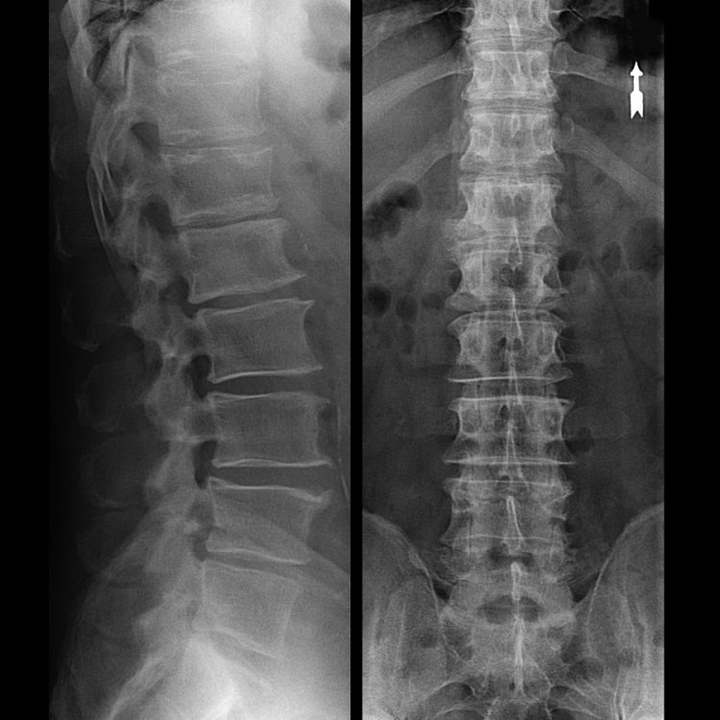

En "Röntgenstrahl" vun der Gebärmutterkierper, a souguer mat funktionnellen Tester fir Flexioun a Verlängerung, weist keen Knorpel, well hiren Tissu Röntgenstrahlen iwwerdréit. Trotzdem, baséiert op der Plaz vun der Wirbelsituatioun, kann een allgemeng Conclusiounen iwwer d'Héicht vun den intervertebralen Scheiwen zéien, d'allgemeng Ausrichtung vun der physiologescher Krümmung vum Hals - Lordose, wéi och d'Präsenz vu marginale Wuesstum op der Wirbelsäit mat längerer Reizung vun hiren Flächen duerch fragil an dehydréiert intervertebral Discs. Funktionell Tester kënnen d’Diagnostik vun der Onstabilitéit an der Gebärmutterhalskierch bestätegen.

Zënter datt d'Discs selwer nëmme mat CT oder MRI gesi kënne ginn, ginn d'Magnéitesch Resonanz an d'Röntgen-Computertomographie uginn fir d'intern Struktur vum Knorpel a Formatiounen wéi Protrusiounen an Hernias ze klären. Also, mat der Hëllef vun dëse Methoden, gëtt eng Diagnostik präzis gemaach, an d'Resultat vun der Tomographie ass eng Indikatioun, a souguer en aktuellen Guide, fir d'chirurgesch Behandlung vun enger Hernia an der Neurochirurgie.